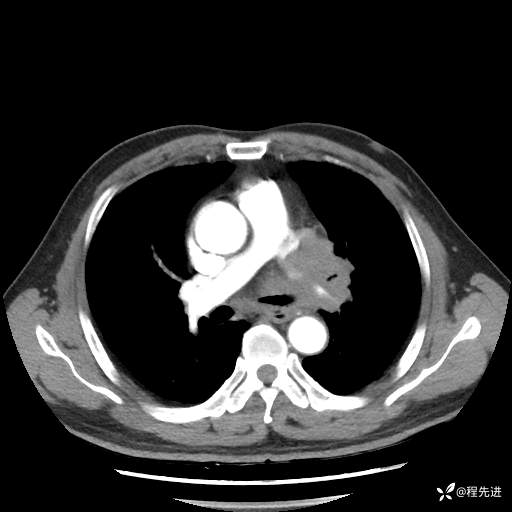

患者性别:男

患者年龄:57岁

简要病史:声嘶2月余

CT平扫+增强: